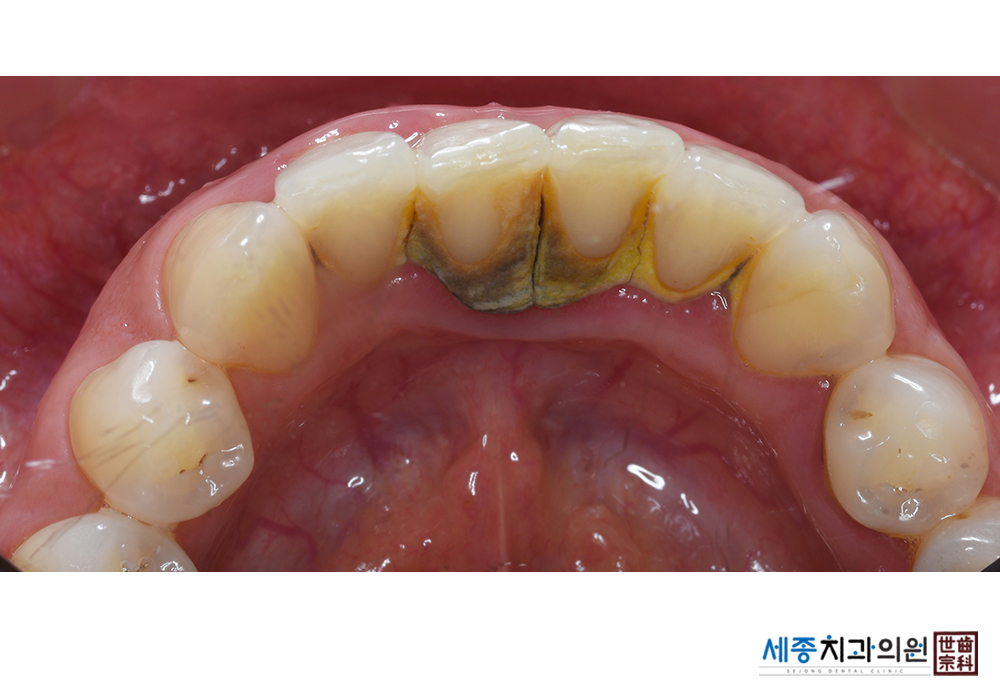

[스케일링] 치주질환 예방 스케일링

치료전 : 2021-01-25

치료후 : 2021-01-25

가글마취&저주파 스켈러를 사용한 스케일링